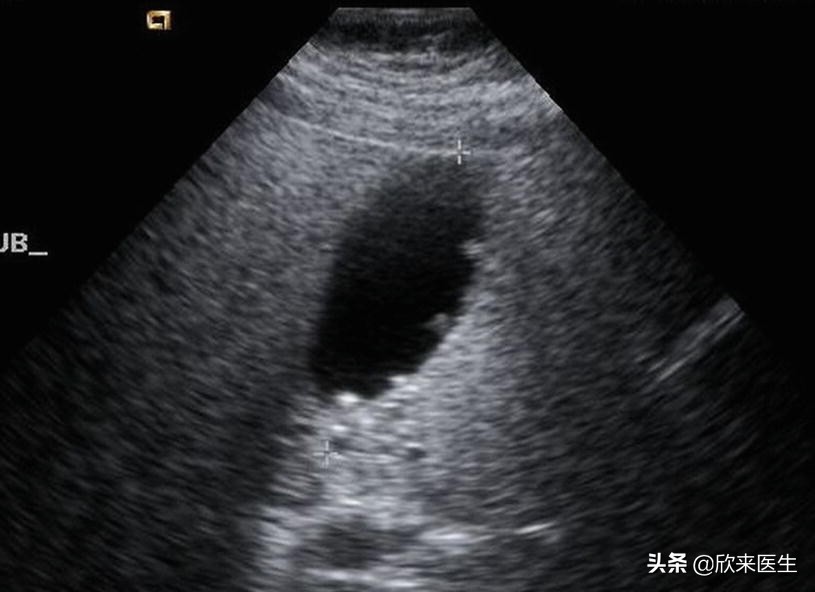

胆囊息肉B超表现